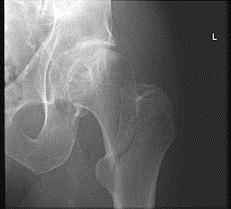

股骨转子间骨折(如图)容易发生的并发症是 ( )A、创伤性髋关节炎B、股骨头缺血性坏死C、损伤性骨化D、髋内翻畸形E、骨折不愈合

问题 股骨转子间骨折(如图)容易发生的并发症是 ( )

选项 A、创伤性髋关节炎 B、股骨头缺血性坏死 C、损伤性骨化 D、髋内翻畸形 E、骨折不愈合

答案 D